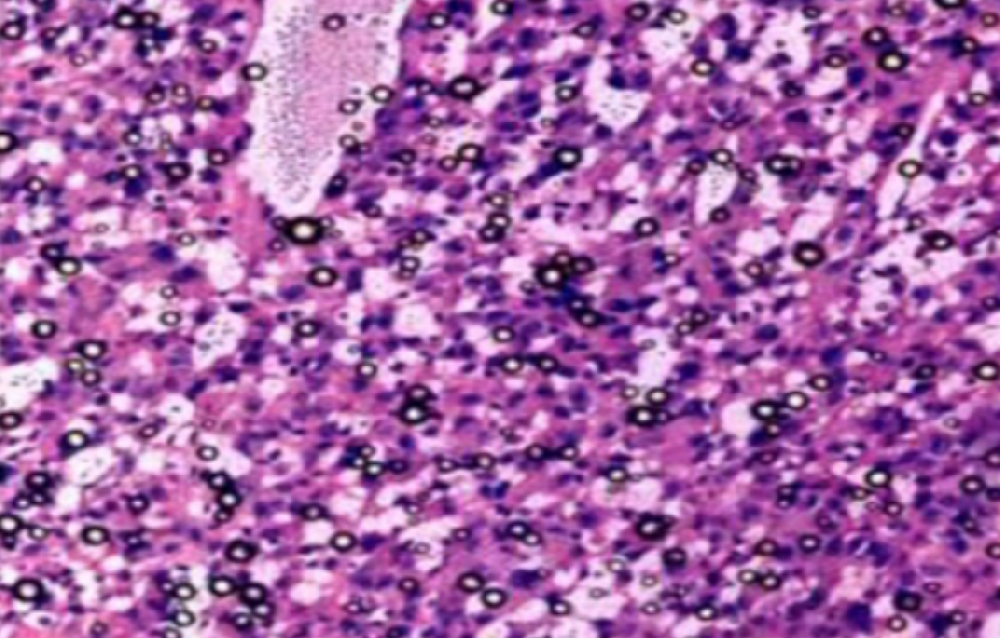

抚州组织病理学实验

实验外包——搞定这几点,轻松做出 "顶配 "免疫组化切片!!

一张高质量的免疫组化染色切片为正确判断染色结果提供了良好的基础和前提。由于免疫组化染色过程中存在很多步骤或环节,每一个步骤或环节都可能影响到染色的最终结果。虽然···